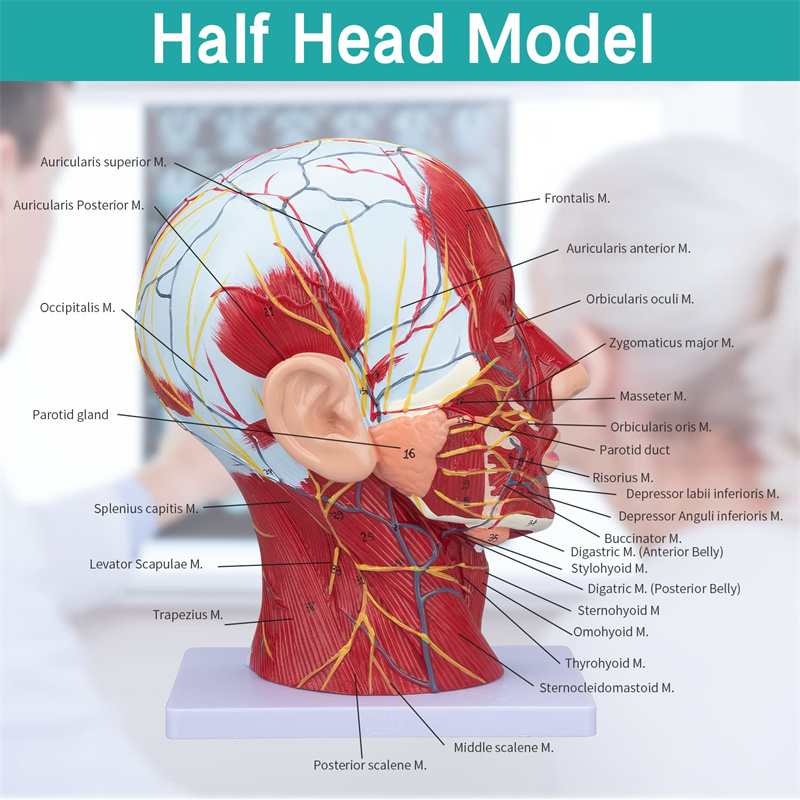

| Awọn ẹya | Awoṣe naa fihan ọrọ ayọ ti agbegbe ti apakan ti inu ati ọrun, ati awọn ẹya ara ti awọn iṣan ara ati awọn ẹya ara, ati awọn ẹya 84 wa ti o nfihan awọn ami lapapọ. |

Awọn ẹya】 o ṣafihan awọn iṣan ti o fara ara ti oju ti o farabalẹ; Awọn ohun elo ẹjẹ ti o dara julọ & awọn iṣan ti oju & scalp; Awọn ẹya inu ti Patiod erumlandi ati oke atẹgun; Eto apakan-ilẹ Sagittal artical ti ọpa ẹhin.

Awoṣe yii fihan awọn alaye ti ọrun-ọrun ati apakan sagittital ti eniyan. pẹlu superficial

awọn iṣan ti oju oju; Awọn ohun elo ẹjẹ ti o ga julọ ati awọn iṣan oju ti oju ati awọsanma; Awọn ẹya inu

ti parotid blandi ati atẹgun oke; Eto apakan-ilẹ Sagittal artical ti ọpa ẹhin.

Awoṣe ṣe afihan ọrọ-ọrọ ti agbegbe ti aarin ati awọn apakan sagittal ita ti ori ati ọrun ati awọn ẹya ara ati awọn ẹya ara ẹrọ ti ofura, pẹlu apapọ awọn olufihan oju opo wẹẹbu 100.

Awoṣe yii jẹ ori ti o tobi pupọ ati awoṣe iṣan ti o ni agbara nla ati eto aarin ti ẹṣẹ parotid ati atẹgun oke, ati apakan apakan apakan Sagitttal ti ọpa ẹhin